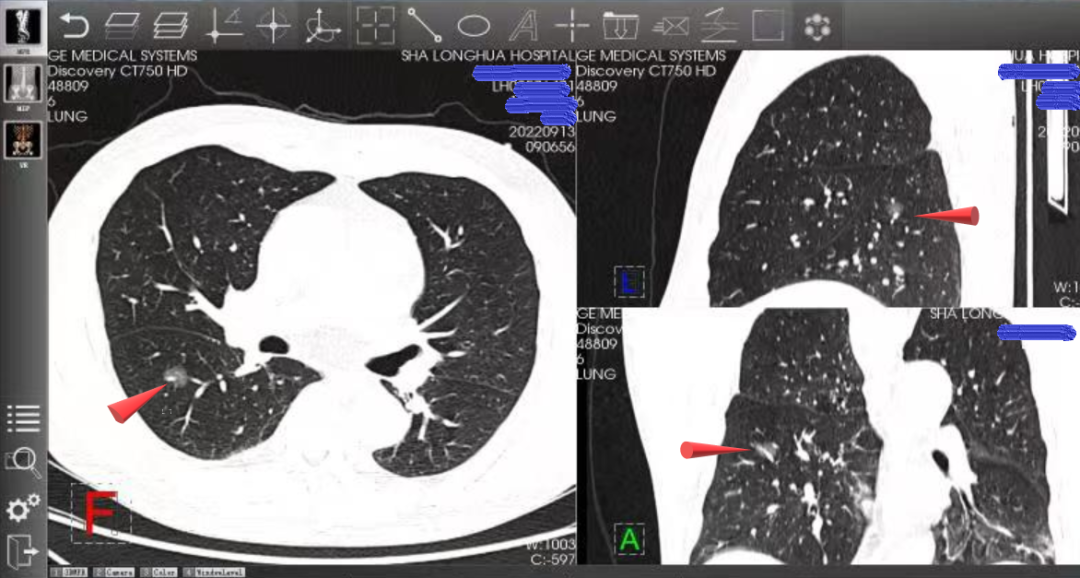

右肺上叶背段毛玻璃结节,经术前评估,考虑该结节恶行可能较大(红色箭头标记处为目标病灶)